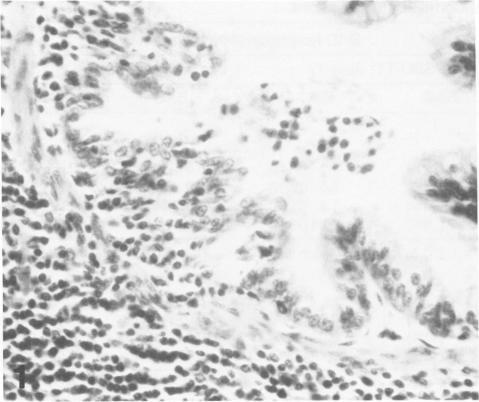

For investigation of the pathogenicity of lentivirus strains, which have distinctly different cytopathic phenotypes in synovial membrane cell culture, plaque-purified, lytic, and nonlytic ovine lentivirus (OvLV) isolates were inoculated intratracheally into two groups of neonatal lambs. Twelve lambs were inoculated with a lytic OvLV isolate and 3 lambs each with two nonlytic OvLV isolates. Five control lambs were inoculated with either virus-free medium or were left uninoculated. In 8 of 12 lambs inoculated with a lytic OvLV isolate mild to severe lesions of lymphoid interstitial pneumonia (LIP) and pulmonary lymphoid hyperplasia developed, 6 of 12 lambs had lesions of pulmonary lymph node follicular hyperplasia, 3 of 9 female lambs had lesions of lymphoproliferative mastitis, 3 of 10 lambs had lesions of lymphocytic/plasmacytic synovitis, and 3 lambs had no lesions. In 3 of 6 lambs inoculated with nonlytic OvLV isolates only mild LIP lesions developed, without concurrent mammary gland or joint lesions. Bronchoalveolar lavage samples from OvLV-diseased lambs contained on average 1.5-fold more numbers of total leukocytes, and 4-fold more numbers of lymphocytes, compared with bronchoalveolar lavage samples of normal lambs. Monoclonal antibodies to ovine lymphocyte surface markers showed that the SBU-T8+ lymphocyte (CD 8 equivalent) was the predominant lymphocyte subset (mean of 65% of total lavaged lymphocytes) in bronchoalveolar lavage samples of 3 diseased lambs. Ovine lentivirus was reisolated from multiple tissues of both groups of OvLV-inoculated lambs, but the percentage of individual tissues infected was greater in lambs inoculated with the lytic viral isolate. Control lambs had no lesions and failed to produce OvLV-specific antibodies or yield OvLV from tissues. All OvLV-inoculated lambs produced either low or undetectable serum virus neutralizing antibodies. In contrast, lambs inoculated with either lytic or nonlytic OvLV produced precipitating antibodies to OvLV glycoprotein and group-specific protein. However, initial detection of precipitating antibodies to OvLV glycoprotein was earlier (mean, 5.8 weeks after inoculation) in OvLV-infected lambs in which severe lymphoproliferative disease developed and delayed (mean, 10.2 weeks after inoculation) in OvLV-infected lambs with mild or no lesions. Together, these results suggest that lentivirus isolates produced disease in a virus strain-dependent manner and suggest that humoral immune responses against OvLV failed to prevent lesion development in lentivirus-infected lambs.(ABSTRACT TRUNCATED AT 400 WORDS)

为研究在滑膜细胞培养中具有明显不同细胞病变表型的慢病毒株的致病性,将空斑纯化的、溶细胞性和非溶细胞性绵羊慢病毒(OvLV)分离株经气管内接种到两组新生羔羊体内。给12只羔羊接种溶细胞性OvLV分离株,给3只羔羊分别接种两种非溶细胞性OvLV分离株。5只对照羔羊接种无病毒培养基或不接种。在接种溶细胞性OvLV分离株的12只羔羊中,8只出现了轻度至重度的淋巴间质性肺炎(LIP)和肺淋巴组织增生病变,12只中有6只出现肺淋巴结滤泡增生病变,9只雌性羔羊中有3只出现淋巴增生性乳腺炎病变,10只羔羊中有3只出现淋巴细胞/浆细胞性滑膜炎病变,3只羔羊无病变。在接种非溶细胞性OvLV分离株的6只羔羊中,3只仅出现轻度LIP病变,无乳腺或关节并发病变。与正常羔羊的支气管肺泡灌洗样本相比,OvLV患病羔羊的支气管肺泡灌洗样本中总白细胞数量平均多1.5倍,淋巴细胞数量多4倍。针对绵羊淋巴细胞表面标志物的单克隆抗体显示,在3只患病羔羊的支气管肺泡灌洗样本中,SBU-T8 +淋巴细胞(相当于CD 8)是主要的淋巴细胞亚群(平均占总灌洗淋巴细胞的65%)。从两组接种OvLV的羔羊的多个组织中重新分离出绵羊慢病毒,但接种溶细胞性病毒分离株的羔羊中单个组织的感染百分比更高。对照羔羊无病变,未产生OvLV特异性抗体,也未从组织中分离出OvLV。所有接种OvLV的羔羊产生的血清病毒中和抗体水平低或检测不到。相比之下,接种溶细胞性或非溶细胞性OvLV的羔羊产生了针对OvLV糖蛋白和群特异性蛋白的沉淀抗体。然而,在发生严重淋巴增生性疾病的OvLV感染羔羊中,针对OvLV糖蛋白的沉淀抗体的初始检测较早(接种后平均5.8周),而在病变轻微或无病变的OvLV感染羔羊中则延迟(接种后平均10.2周)。总之,这些结果表明慢病毒分离株以病毒株依赖的方式引发疾病,并表明针对OvLV的体液免疫反应未能预防慢病毒感染羔羊的病变发展。(摘要截于400字)